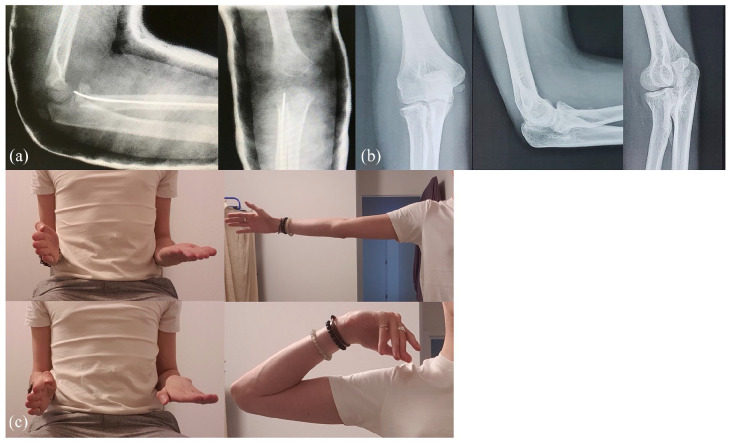

Figure 2.

Case 8. Frontal and sagittal preoperative radiographs (a) of an unhappy triad after reduction of elbow dislocation in an 8-year-old child. Soft tissue depth is increased in the medial compartment and may suggest a third capsule-ligament injury. Peroperative radiographs (b). Frontal and sagittal last follow-up radiographs (c) show good joint congruence after retention of the anteromedial plane but early epiphyseal necrosis of the radius.

Case 15. Sagittal and frontal postoperative radiographs (a). Frontal and sagittal last follow-up (11.5 years after surgery) radiographs (b) show a proximal radioulnar synostosis. Range of motions of elbow at the last follow-up (c) show a limitation of pronation and supination.